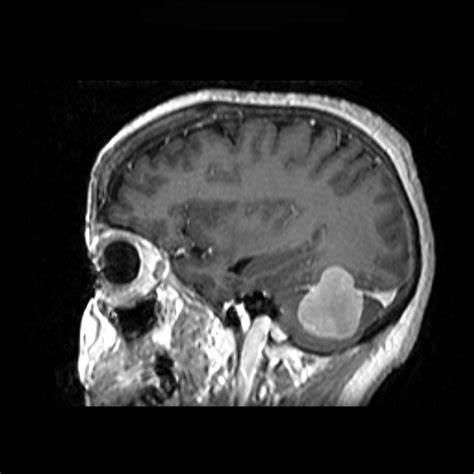

脑膜瘤3cm-4cm严重吗?脑膜瘤不开刀能活多久? 脑膜瘤(Meningiomas)是一种长在脑膜及脑膜间隙的的肿瘤,在颅内常见,80%以上脑膜瘤都是良性的肿瘤。典型的脑...

脑膜瘤 是脑膜的肿瘤,脑膜是覆盖大脑和脊髓的膜。较常见的是良性脑膜瘤或I级脑膜瘤,它们很小,不会像癌性肿瘤一样无限期地生长。非典型脑膜瘤w...

脑膜瘤 是发生在脑膜上的脑瘤,脑膜是包围和保护大脑和脊髓的组织(图1)。尽管大多数脑膜瘤不是癌性的,但当它们生长并压迫大脑或脊髓的重要部位时,...